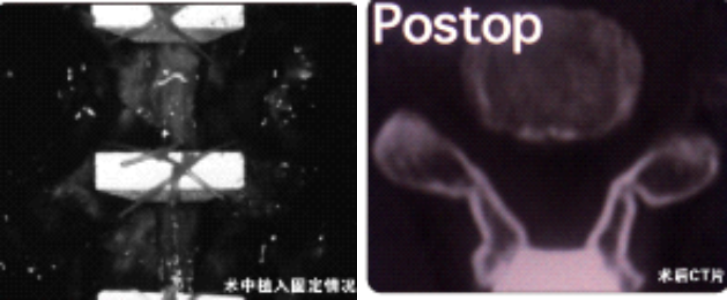

1.对脊髓后部破坏小,有效防止再关门至椎管狭窄

2.为椎管成形术提供了有效的解决方案

3.可融合、稳定性好

● 椎管狭窄症